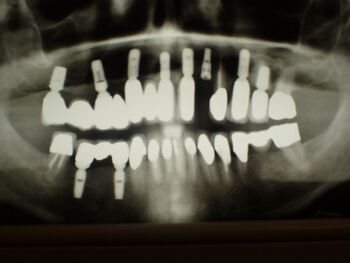

Kieler Patient erhält implantatgestützte Kronenversorgung 22

Dieser Patient ist gesetzlich krankenversichert und hat sich nach und nach inzwischen im CMD CENTREUM KIEL 10 Implantat inserieren lassen.

Das erste im Jahr 2002.